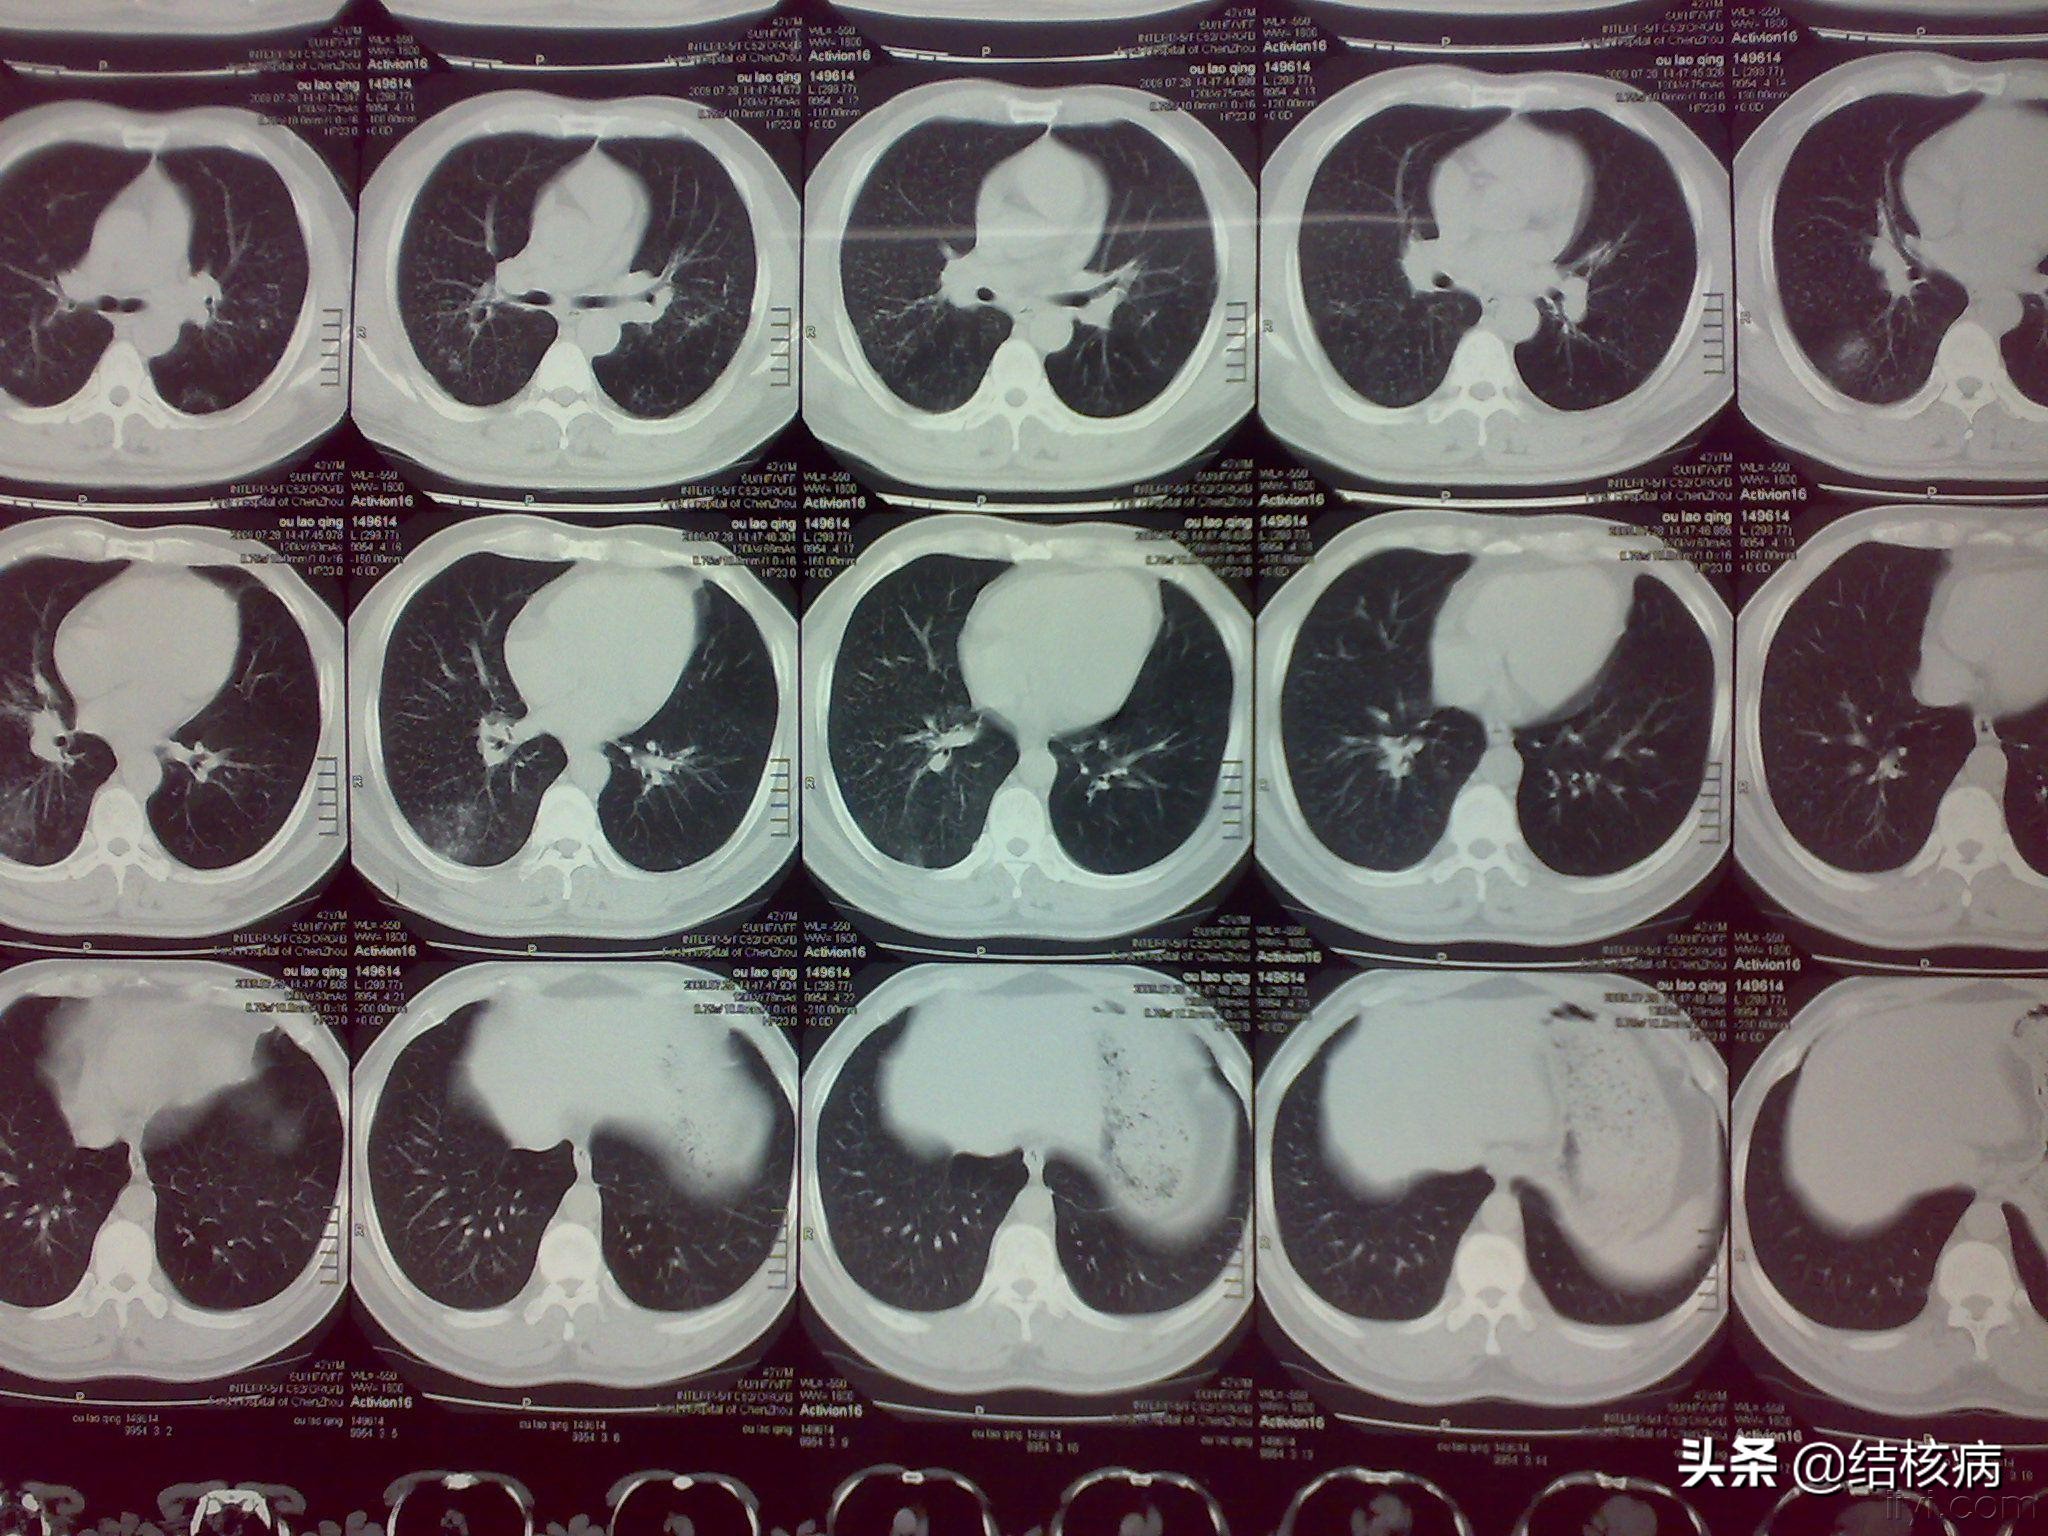

根据病理形态学将矽肺结核分为结合型与分离型。所谓分离型是指矽肺病变和结核病变两者保持各自病变特征,外观上二种病变可明显区分,其结核的病理改变与单纯肺结核相似,即渗出、增生和变性三种病变。其矽肺的病理改变与单纯矽肺相似。分离型矽肺结核-般都发生在早、中期。结合型矽肺结核是矽肺与肺结核两种病变紧密结合在一起,彼此相互掺杂,融为一体,失去矽肺、结核各自病变特征,肉眼外观两种病变不易区分和分割,只有靠镜检才可确定病变性质。结合型矽肺结核其病理形态可分以下几种:

矽肺结核随着病情进展,大多数病例都为结合性,但也有不少病例既有分离型,又有结核型,即混合型。矽肺结核的病理特点为组织破坏严重并容易进、液化出现空洞,病变播散蔓延;局部胸膜增厚明显和肺门常出现淋巴结矽性与结核性增生等病理改变。#结核病##肺结核#